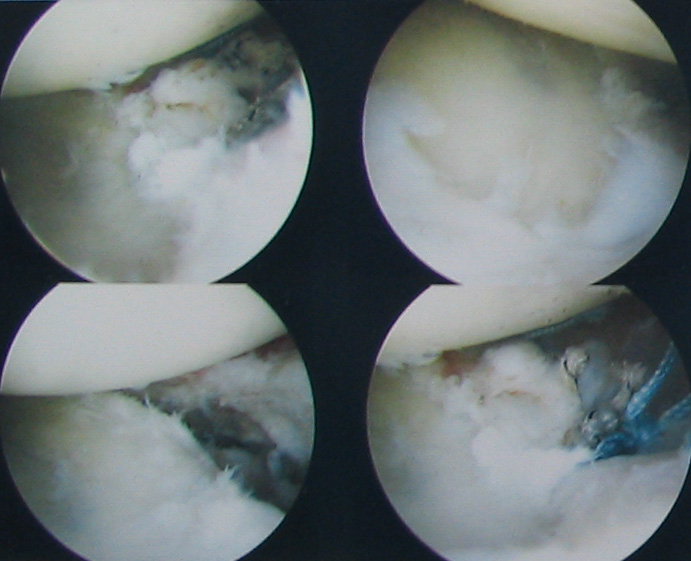

Internal shoulder photos Look away now if you don’t like seeing icky stuff. The following photos are of the internals of my shoulder as seen through an athroscopic probe during a Bankhardt repair performed in late November.